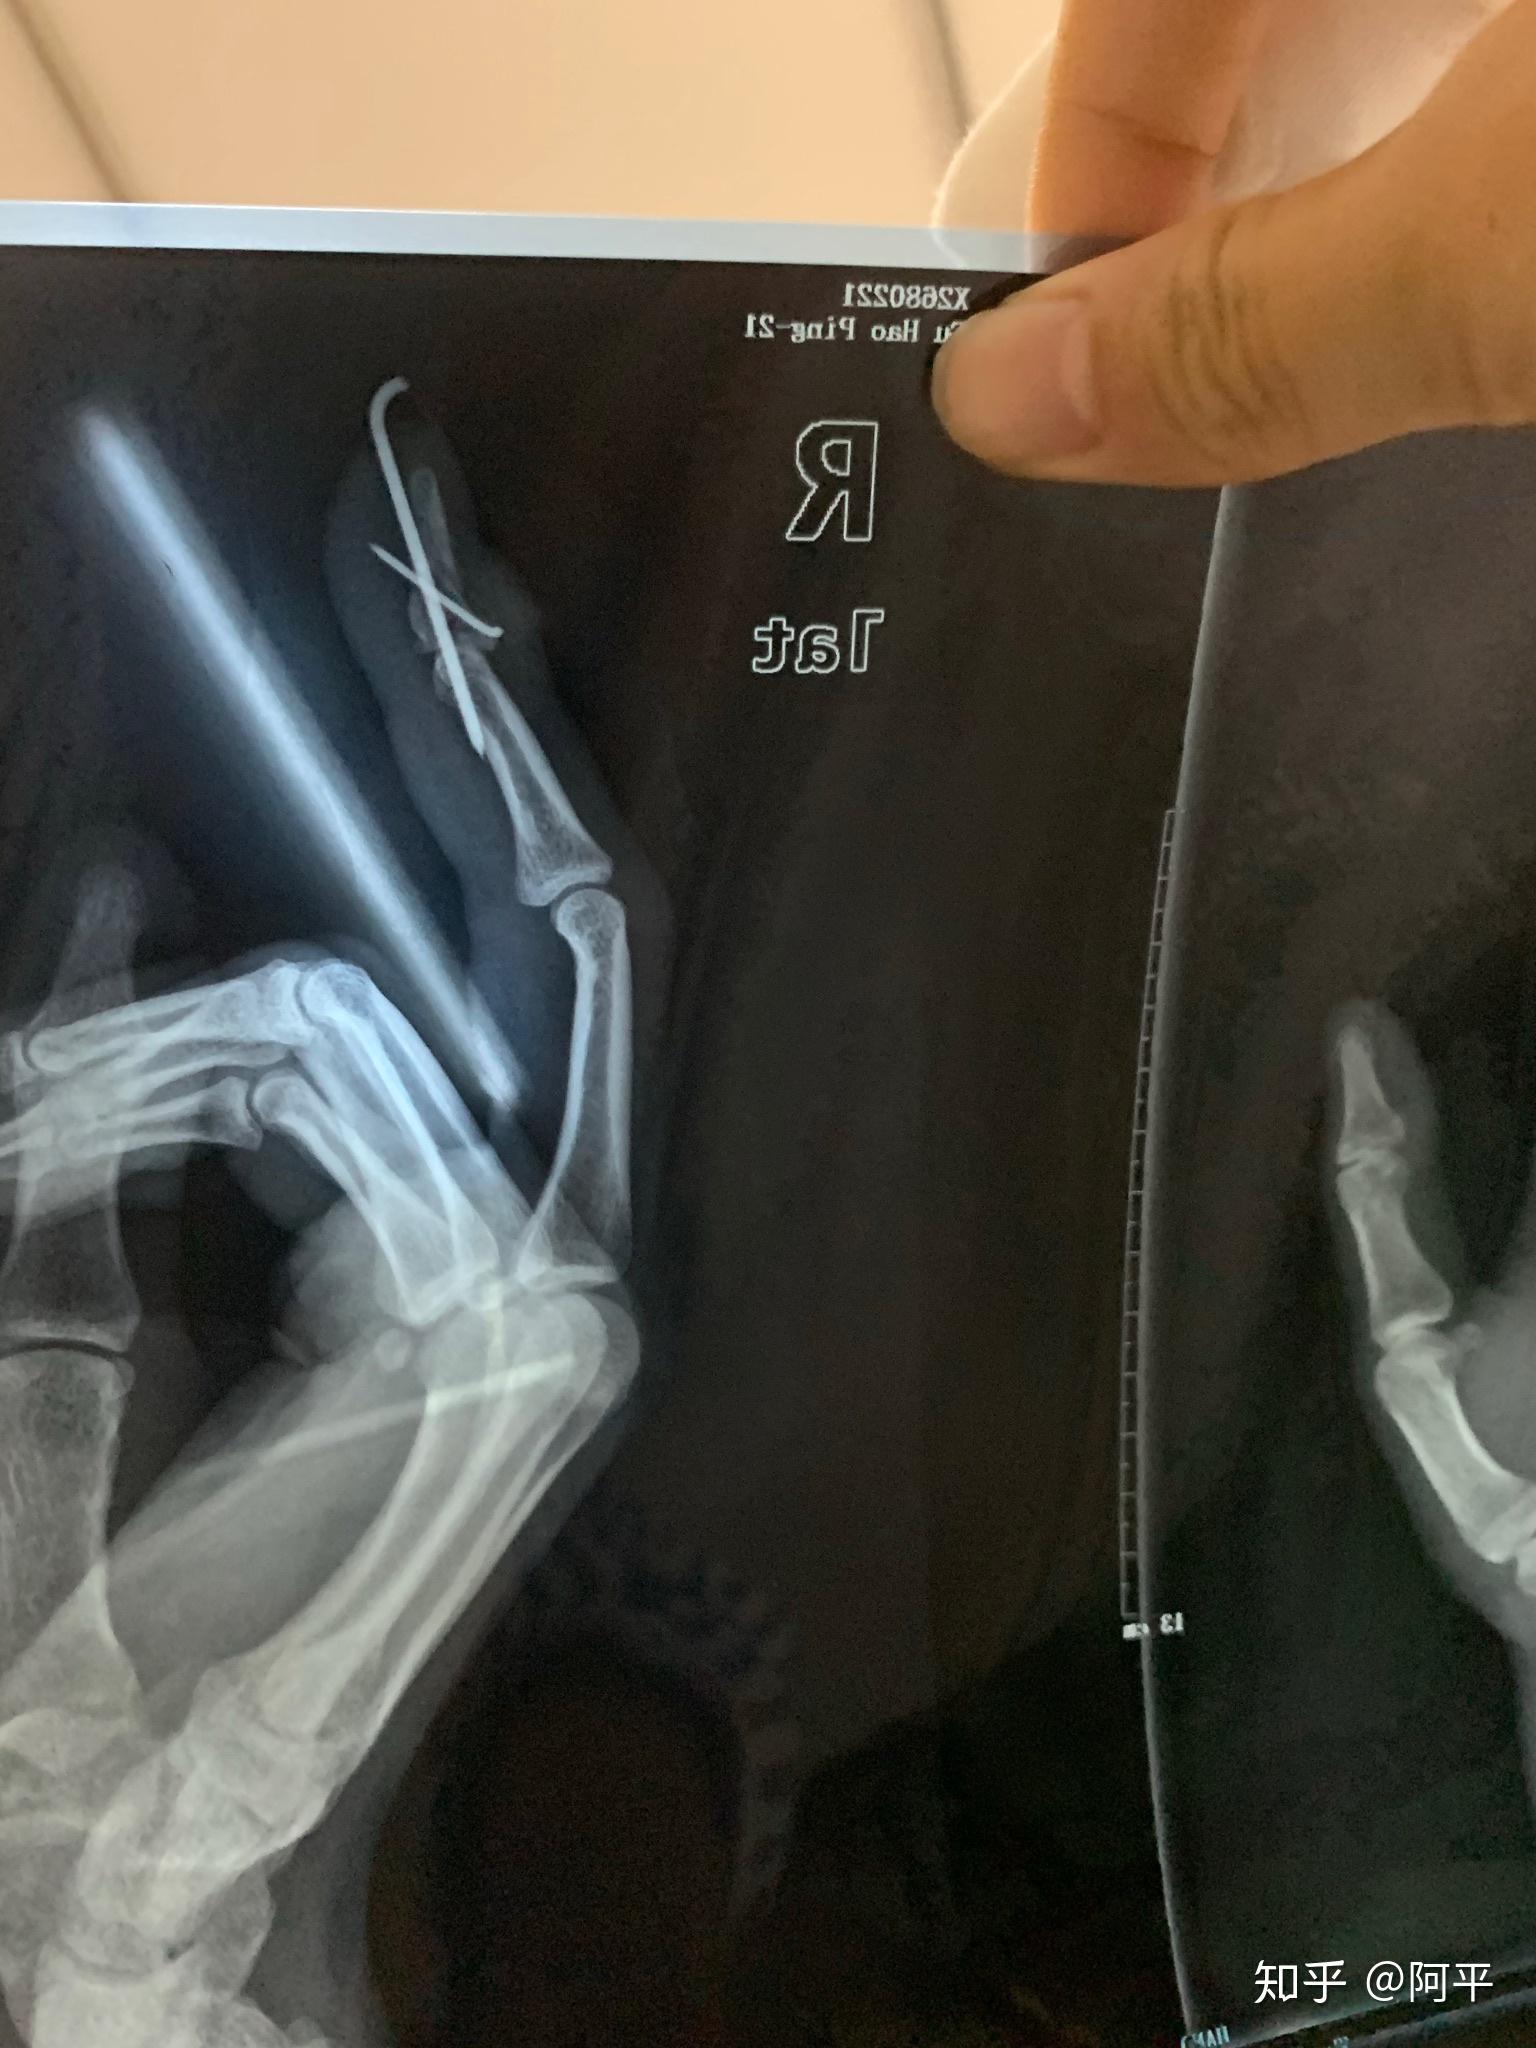

暴力扭伤环指侧副韧带付侧副韧带撕脱断裂伴伸肌腱中央束指点断裂